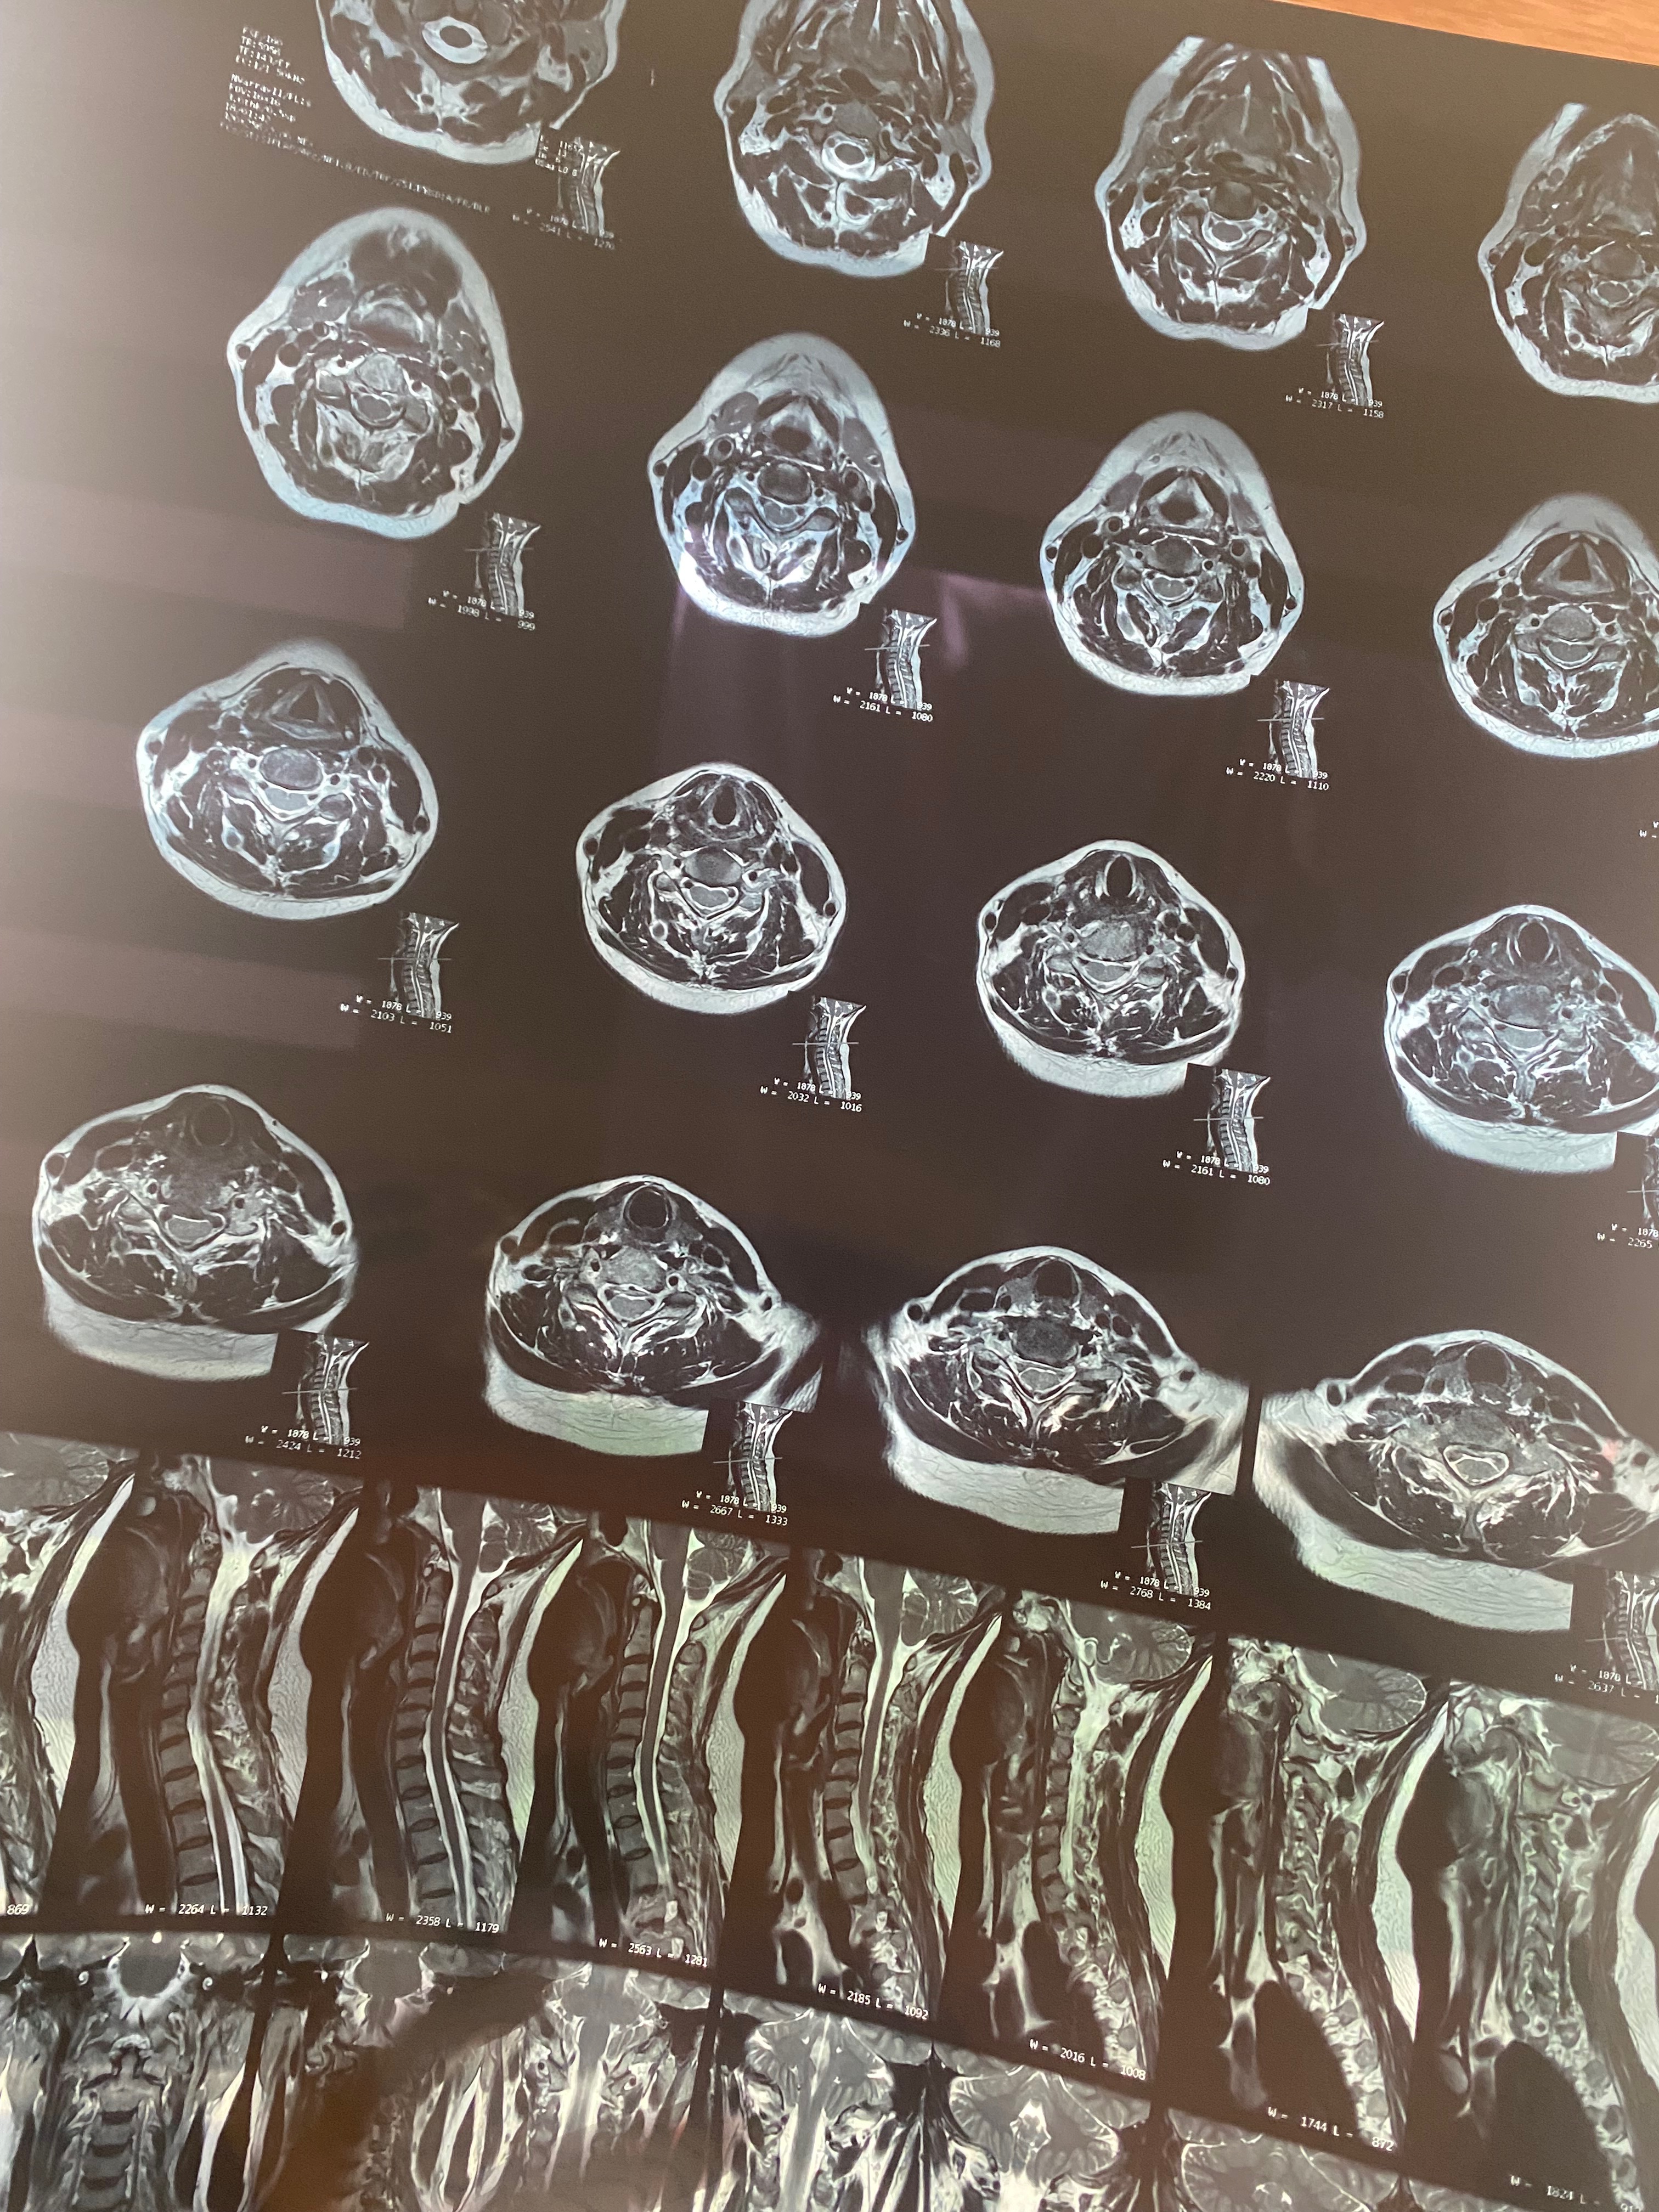

Hace 28 años, mi mamá fue operada de la columna y le colocaron prótesis de metal que, con el paso del tiempo, dejaron de ser funcionales. En los últimos meses, su condición ha empeorado: presenta dolor constante, adormecimiento en las piernas, mareos y una dificultad cada vez mayor para caminar, sentarse y descansar.